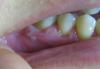

Рузик Опубликовано 5 марта, 2010 Поделиться Опубликовано 5 марта, 2010 (изменено) Здравствуйте. 5 дней назад начались странные вещи с деснами: резко заболели десна, похоже было на васпаление, болели зубы, отдавало болью, немогла нормально жевать пищу, обратилась к стоматологу: сказала, что у меня вся полость рта воспалена, даже язык, прописала:1)3% раствор перикиси водорода полоскать полость рта, затем сразу полоскать хлоргексидином все это 5 раз в день в течении 3-4 дней и одновременно принимать таблетки метронидазол 3 раза в день в течении 7 дней, также накладывать аппликацию из метрогил дент, после 3-4 дней начать полоскать мараславином в течении 10 дней. В торой день полоскаю перекисью и хлоргексидином и принимаю метронидазол, боль утихла, зубы не болят, сейчас пояаились прозрачные пузыри, меня это очень беспокоит, помогите пожалуйста, что это и как лечить дальше? Изменено 5 марта, 2010 пользователем Рузик Ссылка на комментарий

Рузик Опубликовано 8 марта, 2010 Автор Поделиться Опубликовано 8 марта, 2010 (изменено) Мне 23 года, беременности нет. Вот уже три дня как я перестала полоскать полость рта перекисью водорода, и делать аппликацию метрогилом дента. пузырьки лопнули, а на их месте остался гной. вот думаю, может зеленкой помазать или йодом? содой полоскать или алое пожевать или приложить? что посоветуете? также были расширены лимфоузлы рядом с десной на шее, но вроде постепенно проходит, есть легкая стадия простуды. Раньше подобного никогда не было, вообще проблем с зубами нет, легкий кариес и всё, десна не воспалялись. Витамины я принимаю регулярно: компливит. Мараславин не стала покупать, боялась что хуже будет, да и в аптеках советуют стамотофит взять, т.к. первого уже в продаже давно нет. Изменено 8 марта, 2010 пользователем Рузик Ссылка на комментарий